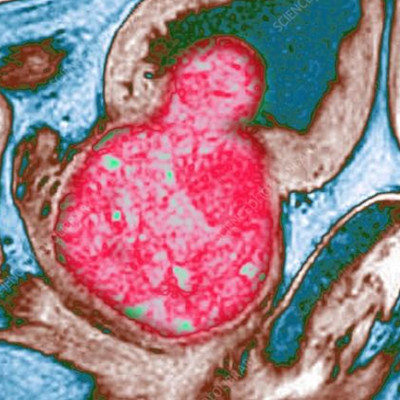

I trattamenti chirurgici tradizionali, come la resezione endoscopica (TURP) o l’enucleazione prostatica con laser ad olmio (HOLEO) o al tullio (THULEP) sono più frequentemente utilizzati per prostate di grandi dimensioni. Tuttavia, spesso questi trattamenti si associato a problematiche della sfera sessuale, soprattutto per quanto riguarda i disturbi dell’eiaculazione dopo l’intervento chirurgico.

I pazienti con prostate di grandi dimensioni possono beneficiare dell’utilizzo di tecniche ablative, come il REZUM e l’ECHOLASER, che pur garantendo buoni risultati in termini di preservazione dell’eiaculazione, risultano molto efficaci nella risoluzione della sintomatologia urinaria, anche in pazienti con prostate di grandi dimensioni. L’urologo esperto deve discutere con il paziente riguardo a tutte le opzioni terapeutiche, spiegando vantaggi e limiti di ogni singola metodica, al fine di trovare il miglior trattamento personalizzato per il paziente.